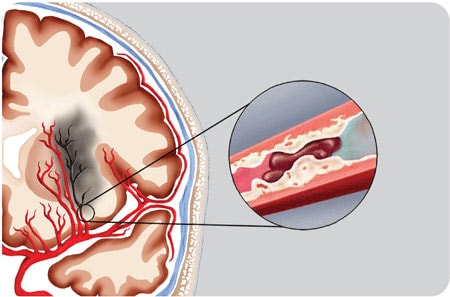

Tắc mạch máu não làm cho vùng não bị tổn thương.

Trong đột quị não thì nhồi máu não chiếm khoảng 80%, xuất huyết não khoảng 20%. Nhồi máu não căn nguyên là do mảng xơ vữa làm tập kết tiểu cầu tạo ra cục máu đông, cục máu này trôi lơ lửng trong lòng mạch gặp đoạn mạch hẹp gây tắc mạch và tổn thương tại cơ quan được cung cấp máu. Người ta lo ngại nhất là tắc mạch ở cơ tim và ở não bộ sẽ dẫn tới cái chết nhanh chóng, qua khỏi cũng khó tránh được tàn phế.

An cung có tác dụng làm tiêu tan mảng xơ vữa (thuốc tương ứng với tác dụng “Khoát đàm” trong Y học cổ truyền) và giãn nở vùng mạch hẹp. Dùng An cung Rùa Vàng kết hợp với Thông Tâm Mạch (có tác dụng chống tập kết tiểu cầu), bệnh nhân sẽ thấy cải thiện sức khỏe rõ rệt, cảm giác khó chịu mỗi khi thay đổi thời tiết sẽ hết, huyết áp ổn định hơn. Liều dùng uống để phòng bệnh theo kinh nghiệm của nhiều bác sĩ và bệnh nhân chia sẻ là: An cung một năm uống 2 lần, chia làm 2 đợt, 6 tháng đầu uống 3 viên, 6 tháng sau uống 3 viên, phối hợp Thông Tâm Mạch ngày 6 viên nang cứng, liên tục 30 ngày uống cùng đợt dùng An cung. Thông Tâm Mạch có tác dụng chống kết tập tiểu cầu, sử dụng để phòng sự hình thành các cục máu đông trong lòng mạch.